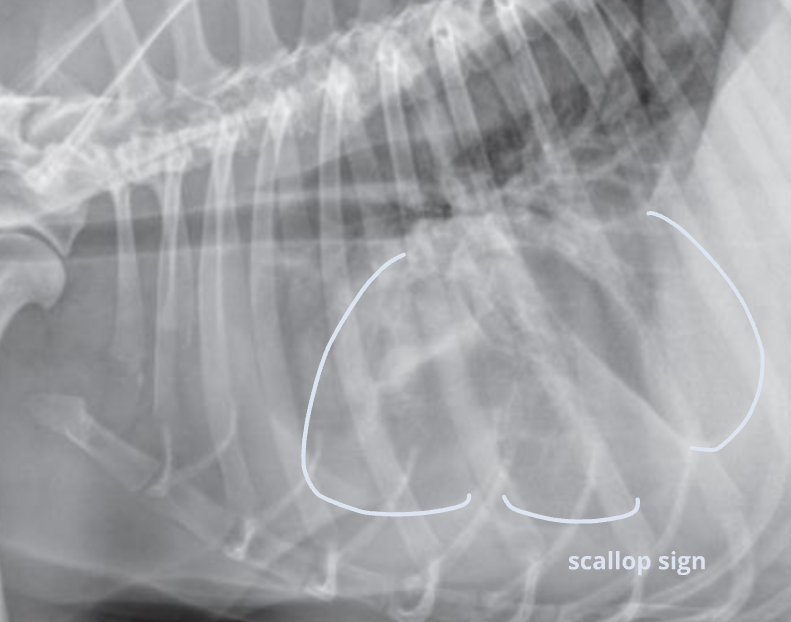

| Radiographic signs interlobar fissure ๋๊ป๊ฒ ๊ด์ฐฐ๋๊ณ , ํ๋ฒฝ์ด ๋จ์ด์ ธ ๋๊ฐ ๊ฒ์ฒ๋ผ ๋ณด์ | Radiographic signs ์ฌ์ฅ์ด ๋ ์๊ณ , ํ๊ฐ ์ชผ๊ทธ๋ผ๋ฆ | |

| - Interlobar fissure widening - Lung retraction - Pleural wall thickening - Scallop sign - Cardiac effacement - Blunt angle | - Retraction of pleural surface - Collapsed lung (โ opacity ์ฆ๊ฐ) | |

![]() | ![]() | |

![]() ![]() | ![]() ![]() | |

![]() |